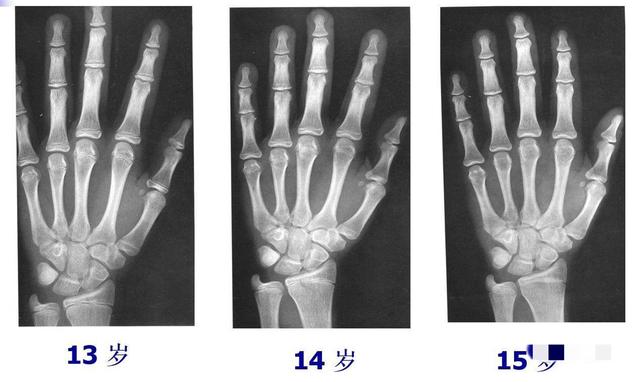

2、测骨龄

这种方式较为准确科学,可到正规的医院给孩子拍个骨龄片子,医生会告诉你是否发育存在滞后的问题。

毕竟现在的孩子生活水平高,普遍存在早熟问题,若骨龄超前,也会导致身高发育受限。